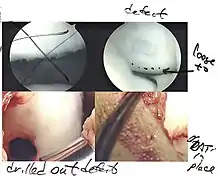

Morselization of the articular cartilage lesion

Harvesting of the articular cartilage and bone

Manual crushing used to make a paste graft

Impacting the paste graft into the morselized defect

The three methods most commonly used in treating full thickness lesions are arthroscopic drilling, abrasion, and microfracturing.

Similar to OATS, arthroscopic articular cartilage paste grafting is a surgical procedure offering cost-effective, long-lasting results for stage IV lesions. A bone and cartilage paste derived from crushed plugs of the non-weight-bearing intercondylar notch can achieve pain relief, repair damaged tissue, and restore function.[61]